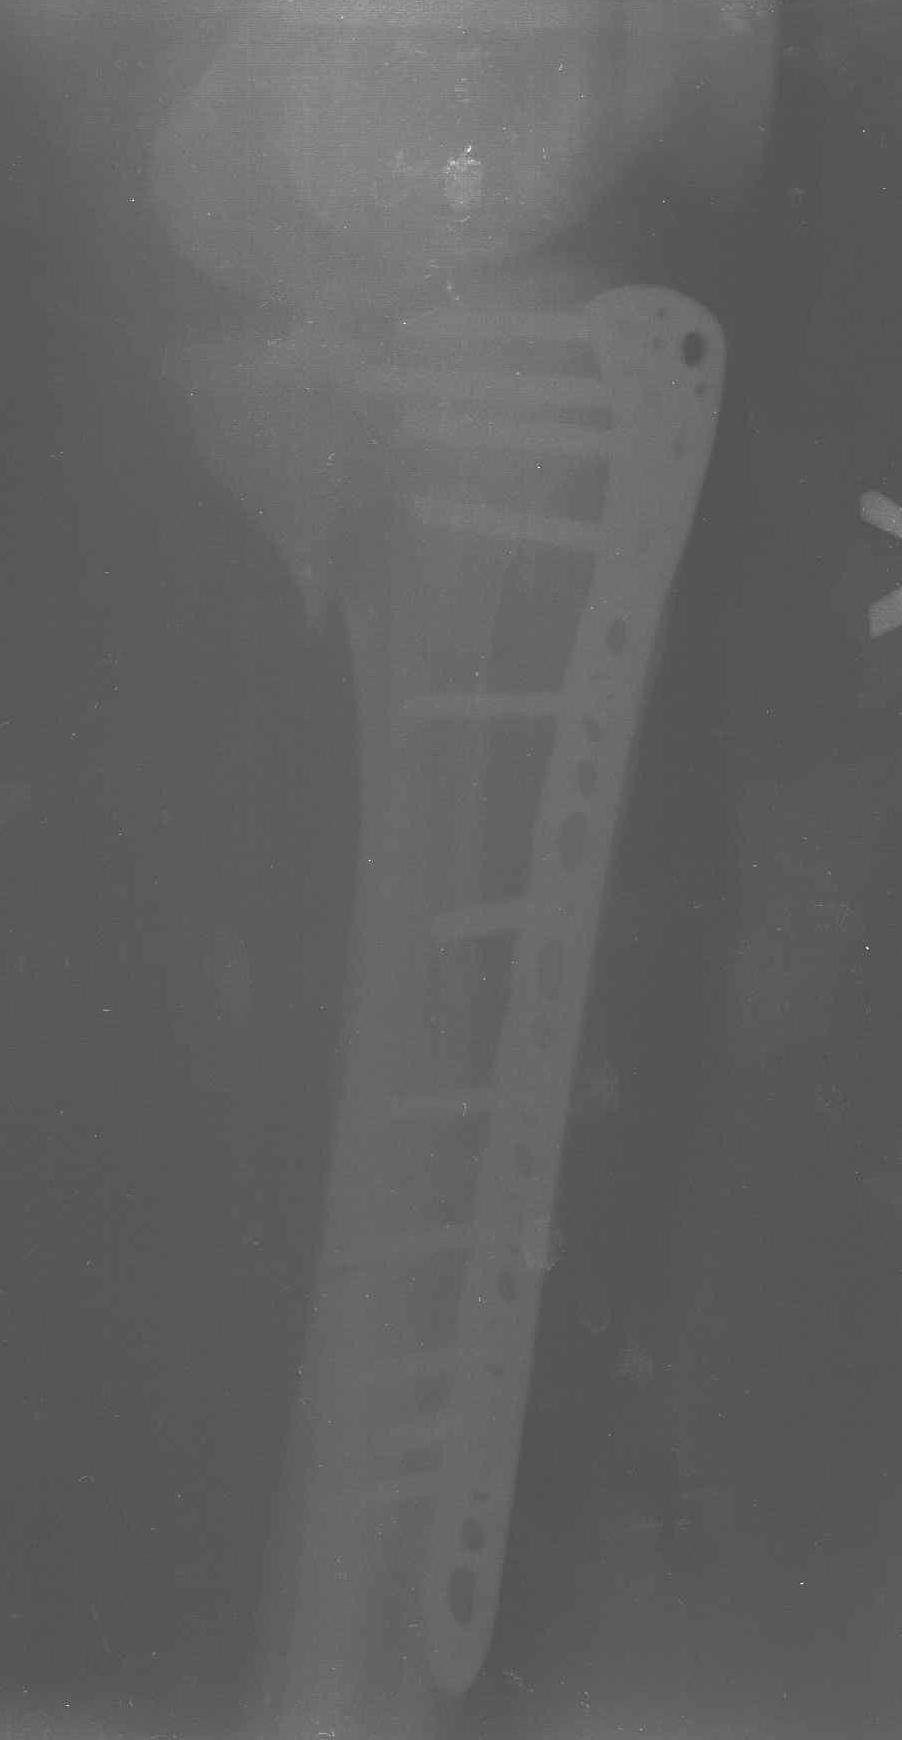

Трудно поверить, что разрекламированная Ортопедическая школа Восточной Украины позволяет такие странные снимки? На прямом снимке сохранен общий контур плато, но не известна судьба импрессии суставной поверхности. На полубоковой?, оставлен без репозиции задне-медиальный отдел, и навряд ли после такой фиксации можно удовлетвориться результатом.

Такая ситуация характерна для многих, когда принимается ошибочное решение, т.е пытаются фиксировать одним имплантом переломы двух мыщелков. Латеральная пластина приемлема только для тех случаев, когда сохраняется интактным медиальный диафизарный кортекс и отсутствует фрагментация на верхушке медиального перелома.

Здесь как раз тот случай, когда результат зависит не только от мастерства хирурга, но и от наличия современных методов исследования. Например, КТ которая поможет рассчитать направления шурупов и установку импланта. Кроме этого, поможет определиться с доступом.

Представленные снимки не информативны, нужны отдельные качественные снимки коленного сустава и голени без ротации.